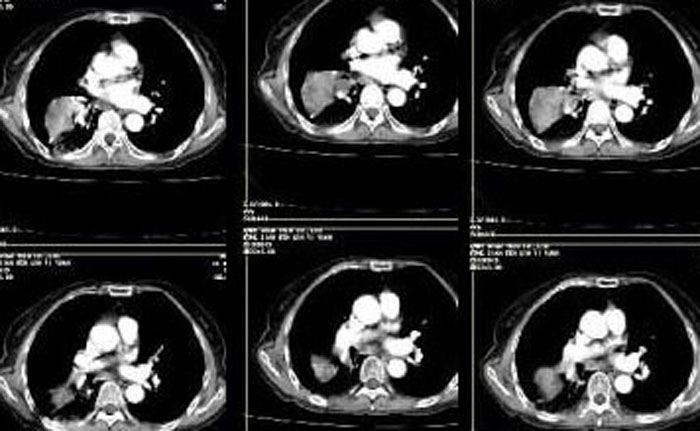

没扫全,肺门纵膈有没有淋巴结?

肺ca可能性大,活检

气管镜

考虑右肺下叶周围型肺癌并阻塞性肺炎。

支持!!